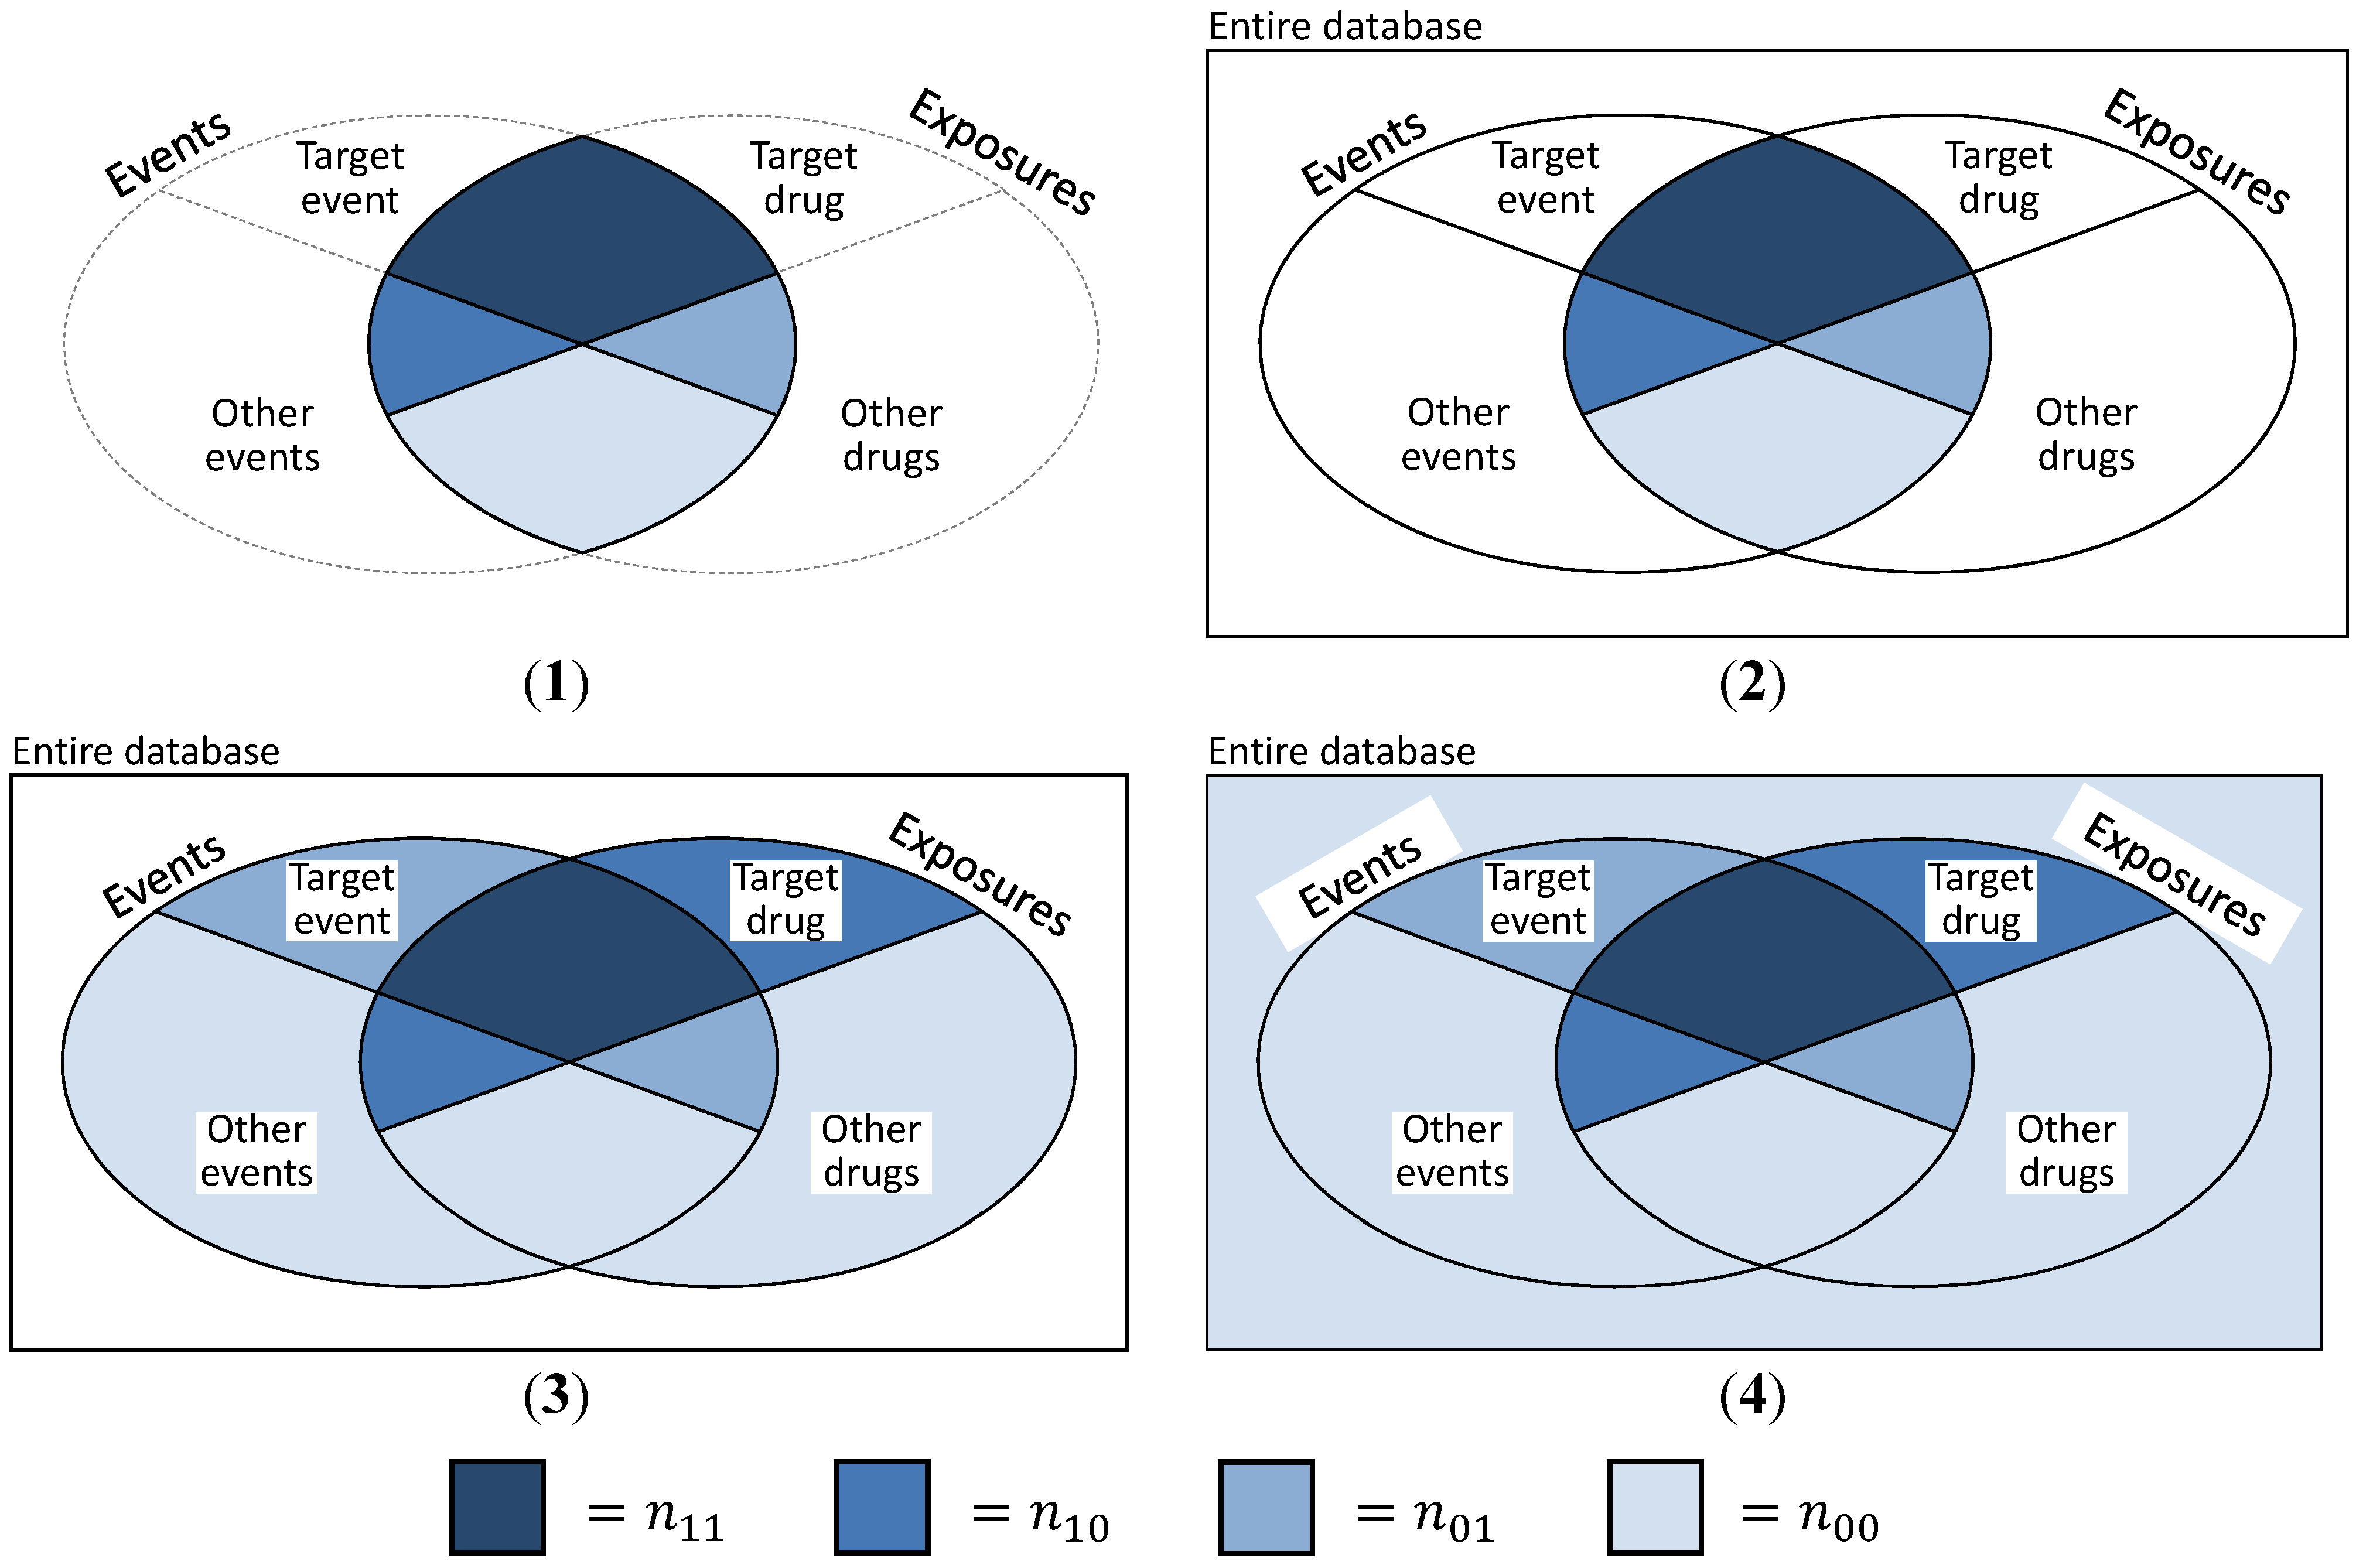

- (a)

- The basic and most obvious approach is to create “pseudo”-SRs, trying to simulate the exact data structure presented in Table 1. Then, n11 is defined as the number of DEC ij, n01 as the number of events j while not under exposure i, n10 denotes all exposure periods to drug i with a different ADR than event j and n00 is the number of non-j events under non-i exposure (cf. Figure 4(2)). This is a coherent and convenient definition, suffering from the major deficit that information on exposures without events and events without exposures is missing. This approach was discussed and implemented by Schuemie [30] and Zorych et al. [35].

- (b)

- Curtis et al. [34] proposed a method of converting longitudinal data to SR with the possibility to additionally include information on non-exposures and non-events by introducing temporal segmentation of the data. They considered each month per subject to be a single report, consisting of all events that the subject experienced during this specific month and all drugs that were consumed that month or the month before. Thus, reports similar to the structure shown in Table 1 can be generated, plus reports that might contain information on exposures without events or events without exposures (cf. Table 3). Here, n11 is defined as before and denotes the number of reports on DEC ij, n10 is the sum of all reports on drug i without ADR j, n01 is—viceversa—the sum of all reports on ADR j without exposure to drug i and n00 the number of reports containing neither drug i nor ADR j (cf. Figure 4(3)).

- (c)

- A closely related approach to take advantage of the longitudinal information, but without imitating a “reporting structure” was described by Schuemie [30] and Zorych et al. [35]. Here, n11 is defined as the number of distinct DECs ij, n10 and n01 stand for the number of all exposure eras to drug i without the occurrence of ADR j or the number of ADRs j not experienced during exposures to drug i, respectively. Finally, n00 is defined as the number of all non-j events that occur during non-i exposure periods, event-free non-i exposure periods and non-j ADRs when not exposed to any drug (also cf. Figure 4(3)).

- (d)

- The final approach uses even more information than the one presented in c). n11 is defined as number of individuals experiencing event j while exposed to drug i, n10 and n01 are defined as number of persons with exposure to drug i and no occurrence of event j, or an experienced event j and no exposure to drug i, respectively. Finally, n00 includes all individuals that were neither exposed to any drug, nor experienced any ADR (cf. Figure 4(4)). Thus, n11 + n10 + n01 + n00 equals the number n of all subjects contained in the database.